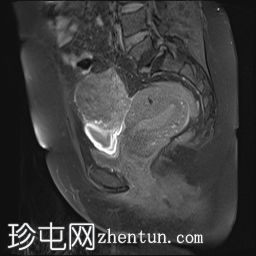

矢状位

T2加权像

可见子宫外腹腔内妊娠囊,内含胎儿组织。

该妊娠囊向后推移子宫,并与剖宫产瘢痕凹陷处紧密相连。

该妊娠囊与相关肠袢无法分离。可见其与性腺血管密不可分,且性腺血管明显突出。

胎盘位于妊娠囊后方,紧贴子宫前壁。

沿妊娠囊下缘可见一处异质性局灶性积液,最大轴向尺寸约为 8.4 × 5.5 cm,T1 加权像呈异质性高信号,T2 加权像呈异质性中等信号,T1 脂肪抑制序列未见信号下降,提示为血液成分。该积液压迫膀胱。

可见周围脂肪间隙呈条索状改变。

左侧卵巢无法辨认。

子宫体积增大,后倾,子宫内膜厚度约 1 cm,子宫下段前壁可见局灶性变薄(既往子宫瘢痕)。子宫连接区完整,未见肌层肿块。可见子宫内膜腔边缘有血性分泌物。